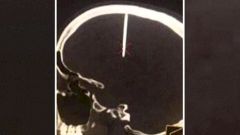

43-летний мужчина обратился в больницу в китайской провинции Хубэй, жалуясь на раскалывающуюся головную боль.

При осмотре врачи обнаружили в его черепе 48-миллиметровый гвоздь (почти 5 см). Узнав об этом, пациент был удивлен, утверждая, что он понятия не имеет, как гвоздь попал ему в голову.

Пациент отправился в город Ухань — столицу провинции Хубэй. Его ждет операция по извлечению гвоздя из черепа.